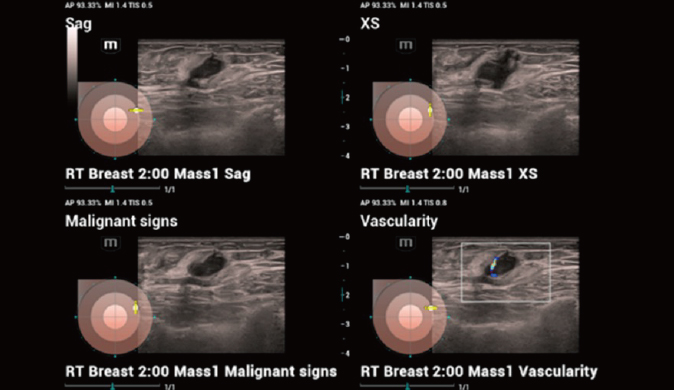

- Smart Breast: Sistema que analisa lesões mamárias automaticamente, otimizando diagnósticos e relatórios.